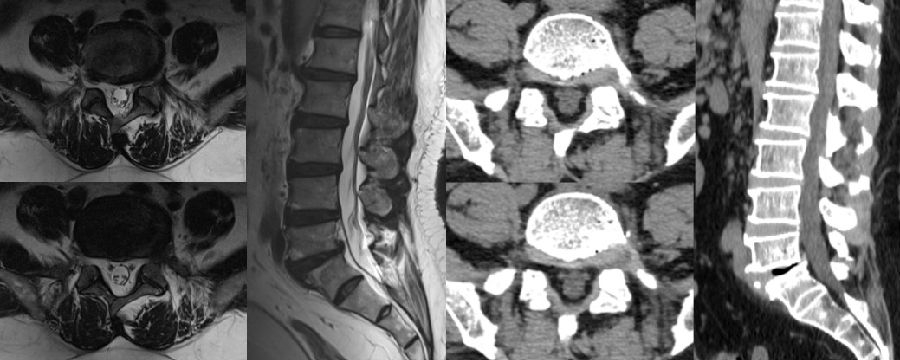

病例(减压不彻底,椎间盘残留)

男,73岁。

主诉:腰痛2年、加重伴右下肢疼痛麻木4个月,右足底、小腿后外侧为著。

术后右下肢症状无明显改善

思考和建议

减压区域应达到椎弓根中段,侧隐窝、椎间隙以及椎间孔内部3个区域都应充分减压

七、术后椎间盘囊肿

病例

男,31岁。

主诉:腰痛伴右下肢疼痛5月,加重2月。

查体:疼痛放射至右侧臀部、大腿外侧、小腿外侧。